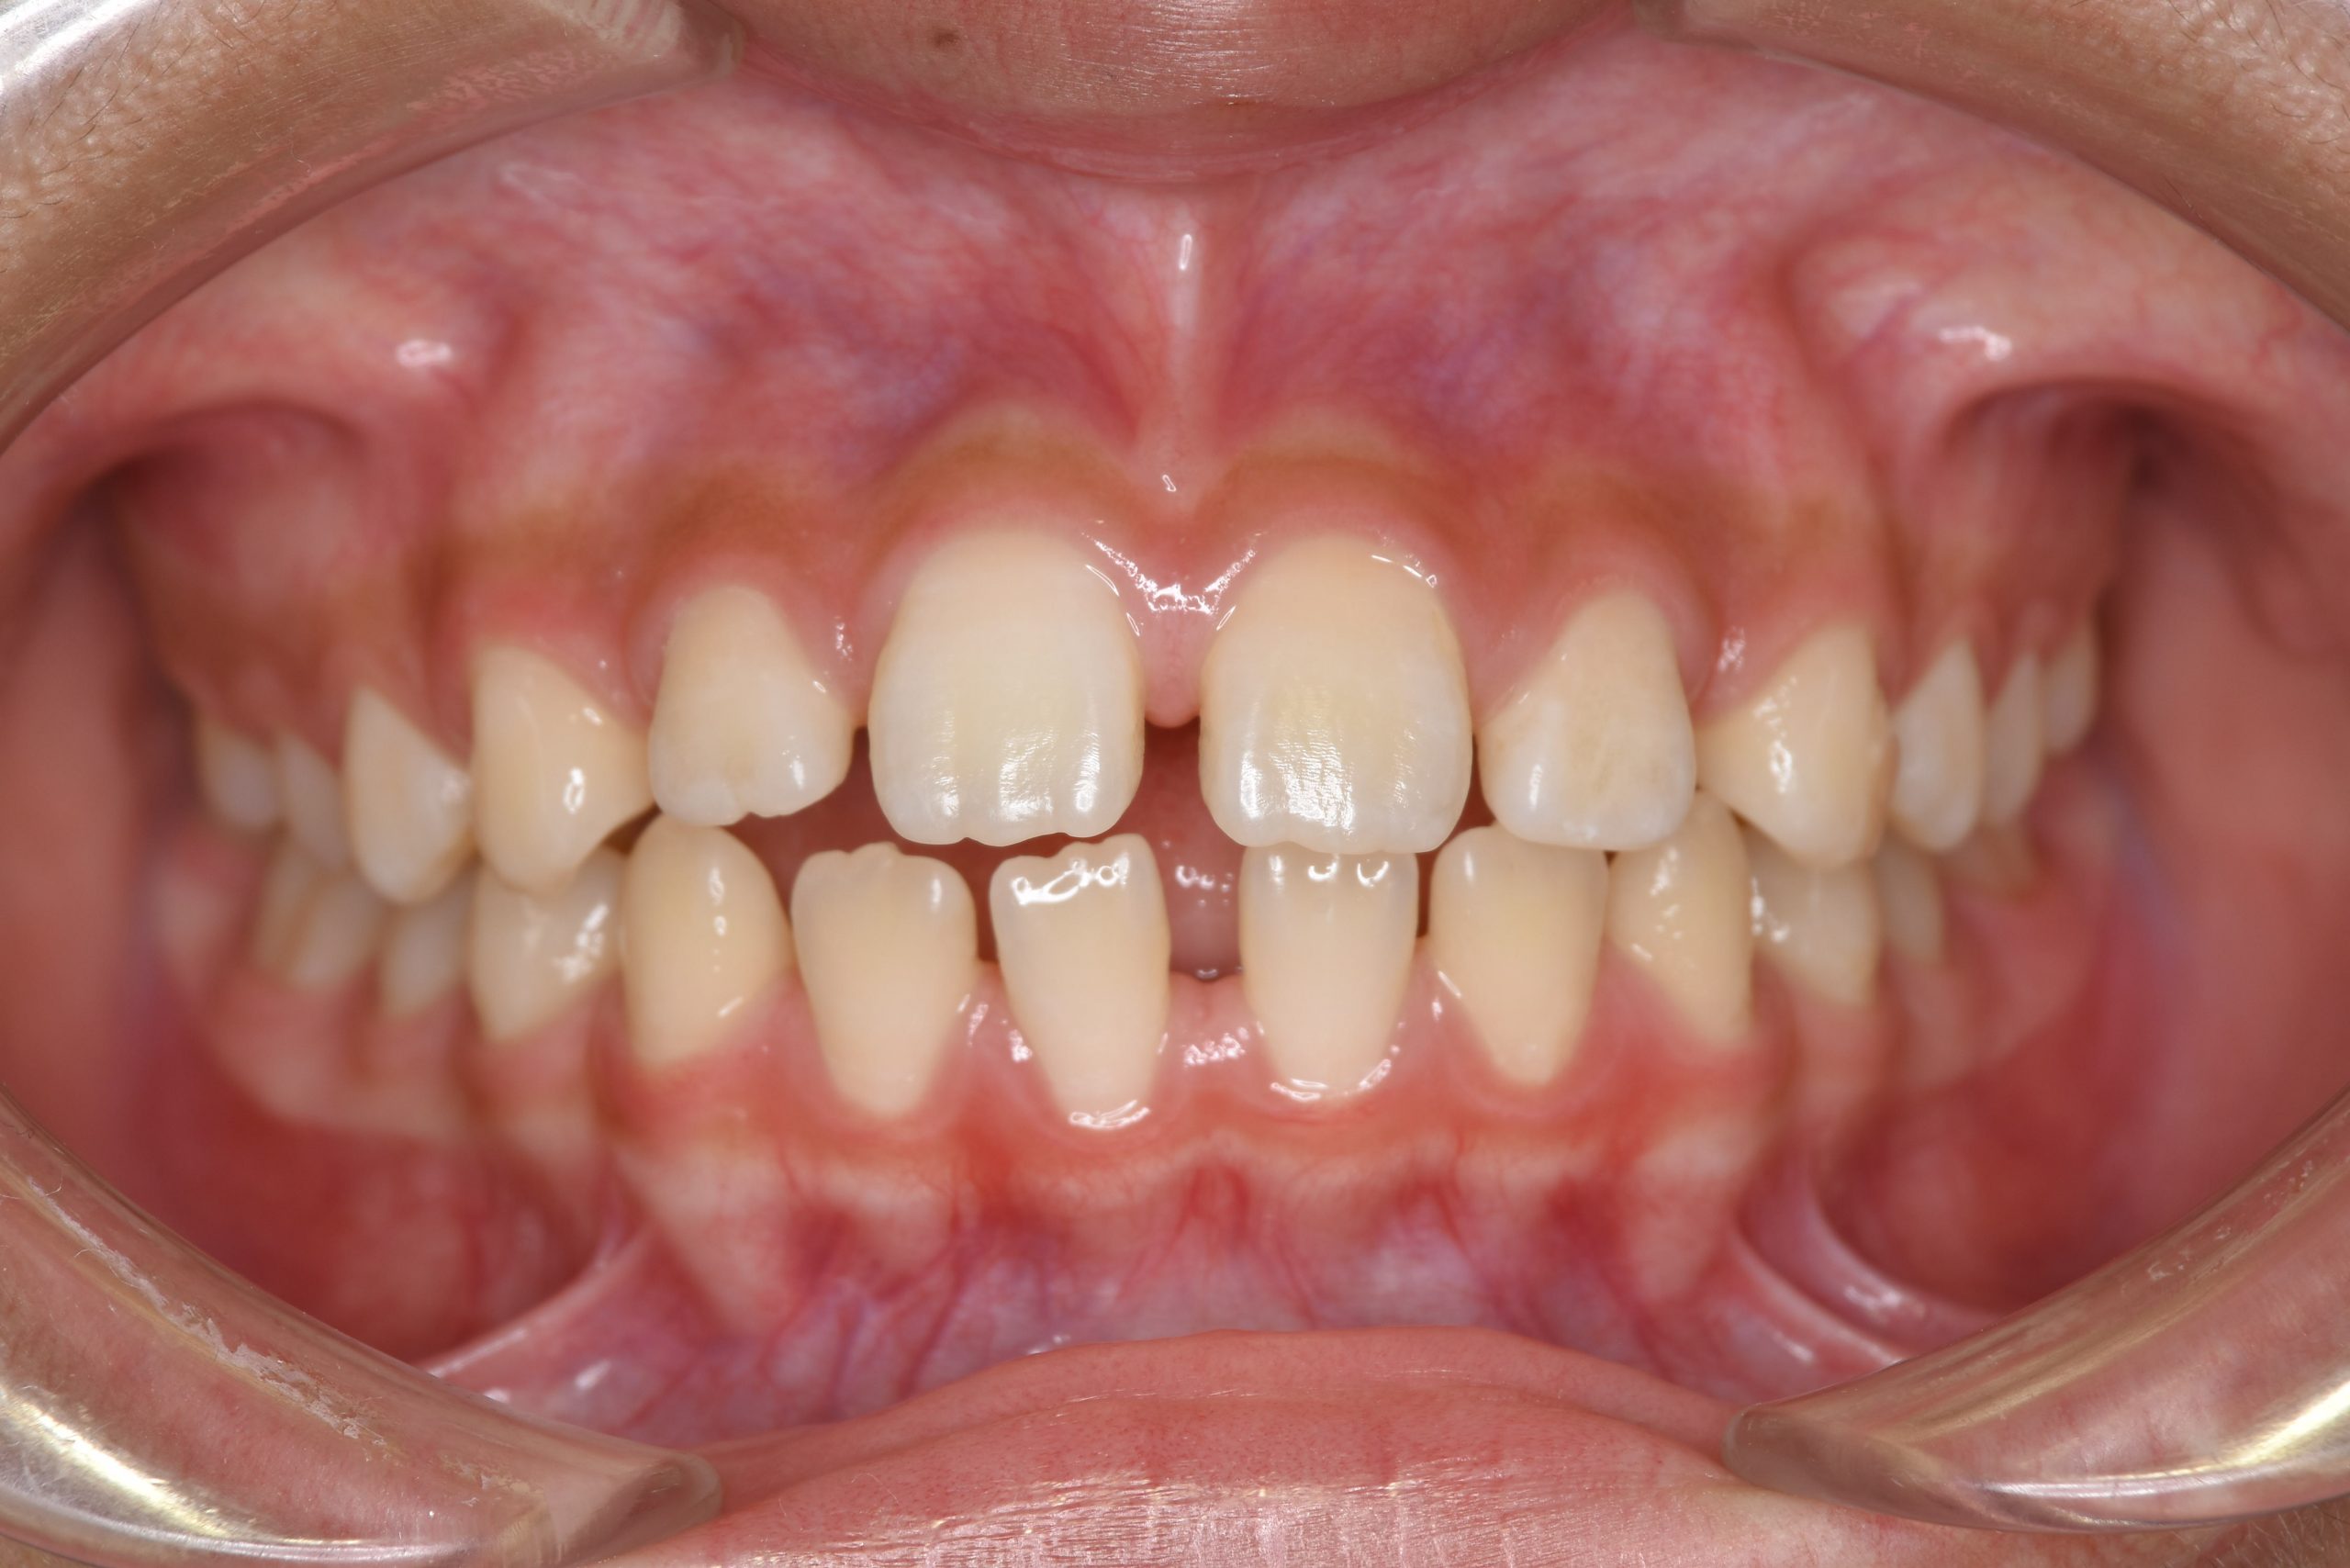

アフター

ワイヤー矯正治療|症例_681

主訴 上前歯が出ている|よく口が開いている

施術内容 上顎急速拡大装置と下顎リンガルアーチを用いて上下顎骨を拡大した。

その後マルチブラケット装置を用いて

非抜歯で歯牙を配列し良好な咬合を獲得した。

鼻閉症状は改善した。

治癒期間 2年10か月間